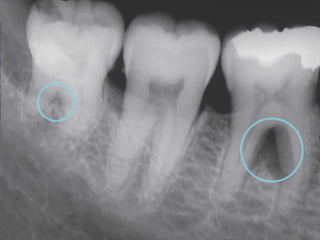

Diagnosis

• The following parameters should be recorded

to evaluate the amount of tissue loss in

periodontal disease and also to identify the

apical extension of the inflammatory lesion

 pocket depth (probing depth)

 attachment level (probing attachment

level)

 furcation involvement (

measured with nabers probe)

 Radiographs

Radiographs

periapical

bitewing